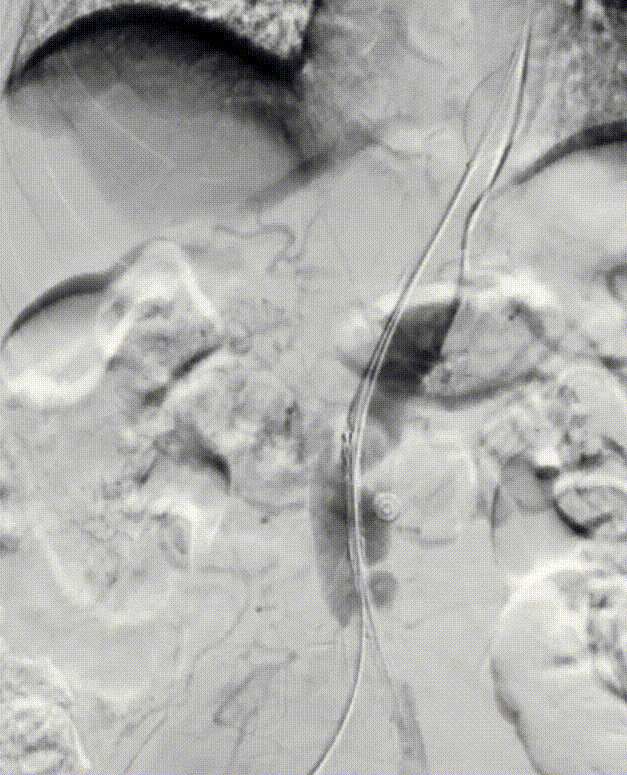

5. 经右侧股总送入泥鳅,再通过泥鳅输送另一个MOB球囊在原球囊远端,尝试将近端的球囊回收,同时展开远端球囊,在远端球囊被造影剂完全展开贴合血管壁以前,将原MOB球囊撤出。

gore医疗怎么样「漫腹精论」髂合时宜 精益求精——双MOB球囊导管辅助腹主动脉覆膜支架急诊治疗破裂巨大髂动脉瘤_https://www.jmylbn.com_新闻资讯_第16张

gore医疗怎么样「漫腹精论」髂合时宜 精益求精——双MOB球囊导管辅助腹主动脉覆膜支架急诊治疗破裂巨大髂动脉瘤_https://www.jmylbn.com_新闻资讯_第17张

6.将右侧球囊往上输送至高于肾动脉的位置以留出空间进行支架输送等步骤,因血流湍急,球囊未能实现在理想位置的展开以进行近端血流阻断

7. 重新送入左侧球囊至右侧球囊远端,对右侧球囊内造影剂进行小部分回抽,使左侧球囊通过球囊与血管壁的间隙继续往近端输送,充盈左侧球囊使其部分展开,捏住左侧球囊输送杆,维持左侧球囊位置,降低右侧球囊受到的血流压力。

8. 将右侧球囊继续往近端推动,超过肾动脉以及经左锁骨下动脉预置的造影椎管,充分使球囊充盈阻断血流,此时能实现右侧球囊在高于肾动脉的理想位置固定。

gore医疗怎么样「漫腹精论」髂合时宜 精益求精——双MOB球囊导管辅助腹主动脉覆膜支架急诊治疗破裂巨大髂动脉瘤_https://www.jmylbn.com_新闻资讯_第18张

gore医疗怎么样「漫腹精论」髂合时宜 精益求精——双MOB球囊导管辅助腹主动脉覆膜支架急诊治疗破裂巨大髂动脉瘤_https://www.jmylbn.com_新闻资讯_第19张

9. 随后将左侧球囊回收后进行回撤,直至右侧球囊远端,对右侧球囊内造影剂进行小部分回抽,使左侧球囊顺着导丝通过球囊与血管壁的间隙,继续往远端输送左侧球囊,等左侧球囊顺利通过右侧球囊远端后,立即把右侧球囊充盈,充盈后将左侧球囊完全退出DSF鞘管。